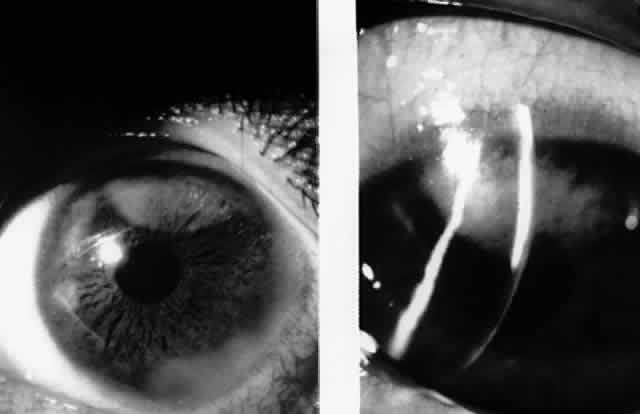

CONJUNCTIVA AND CORNEA There is increasing clinical and laboratory evidence suggesting that EBV is capable of infectingsusceptible cells in the ocular surface epithelia. Expression of CD21, the putative EBV receptor, has been detected in conjunctival and corneal epithelial cells.65 EBV genomic sequences have been detected in 10% of normal corneal epithelial specimens.30 Using highly sensitive reverse transcriptase PCR, EBNA-1 mRNA sequences, but not active latent or lytic cycle associated gene sequences, were detected in 95% of human conjunctival epithelial specimens obtained by impression cytology.31 Taken together, these results suggest that the ocular surface epithelia are sites of EBV persistence following primary infection. Numerous cases of conjunctivitis occuring in patients with IM syndrome were reported prior to the availability of specific tests to confirm a clinical diagnosis of IM.66 More recently, conjunctival involvement has been reported in patients with serologically confirmed IM. In 1981, Meisler and associates reported a case of a unilateral conjunctival inflammatory mass and enlarged preauricular lymph node in an 11-year-old boy with acute IM.67 The conjunctival lesion was biopsied, and an intense lymphocytic infiltrate with occasional multinucleated giant cells was observed in histologic sections. Wilhelmus reported a case of unilateral keratoconjunctivitis in a 16-year-old girl with acute IM.68 This patient had a follicular conjunctivitis and preauricular lymph node. Virus was cultured from the tears and conjunctiva of this patient. Matoba and associates also noted conjunctival inflammation consisting of mild hyperemia occasionally accompanied by a follicular tarsal conjunctival response in a series of patients with IM.69 Gardner and co-workers recently reported a case of a bulbar conjunctival nodule associated with unilateral enlarged preauricular and submandibular lymph nodes in a 38-year-old patient with acute IM. Mature lymphocytes and plasma cells were noted in histologic section, and scattered cells in the lesion stained positively for EBV active latent cycle antigens (LMP-1 and EBNA-2).70 The first reported association between IM and keratitis came from Payrau and Hoel in 1958.71 The authors described a patient with IM, follicular conjunctivitis, and in a single quadrant of one cornea, interstitial infiltrative keratitis. However, theputative association between IM and corneal stromal inflammation in their case is in doubt, because they also found a corneal foreign body within the area of keratitis. In 1980, Pinnolis and colleagues described a 16-year-old boy with classical heterophil antibody-positive (IM) who, upon discontinuation of oral corticosteroids, developed bilateral “nummular interstitial keratitis” without stromal vascularization.72 The corneal opacities were bilateral and symmetric unlike herpes simplex (HSV) and varicella-zoster virus-induced disease, and deeper within the corneal stroma than the subepithelial infiltrates of adenovirus keratitis. Acute and convalescent serologies by indirect immunofluorescence for specific antibody against EBV capsid antigen showed a greater than fourfold rise consistent with acute infection, while antibody titers by complement fixation for HSV, adenovirus, mumps, cytomegalovirus, influenza virus, and respiratory syncytial virus remained low or undetectable throughout the illness. In 1986, Matoba and associates reported 7 patients with purported EBV stromal keratitis, but only 3 of the patients had clinical symptoms of IM or evidence of recent seroconversion.69 In one of the patients, heterophil antibody-positive IM preceded by 1 week the onset of chronic multifocal keratitis. When the authors first examined the patient in referral 9 months later, they found multiple, discrete, anterior stromal opacities in the patient's left eye. In another patient, bilateral, patchy, deep peripheral infiltrative keratitis and a fourfold decrease in antibody against EBV viral capsid antigen were documented at the time of referral 5 months after an “infectious mononucleosis-like illness” associated with bilateral red eyes and photophobia. In another patient, the authors state that IM preceded subepithelial infiltrative keratitis in the left eye by 1 month. When examined 8 months after onset of the keratitis, the patient's left cornea showed features of multifocal anterior stromal and deep peripheral stromal keratitis. Although the other 4 patients in this series did not show evidence of recent EBV seroconversion, their keratitis appeared similar to that of the patients with documented IM. On clinical grounds alone, Matoba and associates postulated that the development of EBV keratitis did not depend on recent EBV infection, but could occur in the chronic carrier state. To summarize the authors' findings in the combined group of 7 patients, the interstitial keratitis appeared in 4 patients as unilateral, multifocal, discrete, sharply demarcated, anterior stromal opacities, 0.1 to 2 mm in diameter, with either a blotchy pleomorphic (Fig. 2) or granular ringlike appearance (Fig. 3), in two patients as bilateral, multifocal, full-thickness or deep stromal peripheral infiltrates reminescent of luetic keratitis (Fig. 4), and in 1 patient with features of both. No patient tested had showed serologic evidence of acute systemic HSV or adenovirus infection. Both patients with keratitis restricted to the peripheral cornea had bilateral disease but lacked serologic evidence for syphilis (nonreactive MHA-TP). Five patients had mild or moderate corneal stromal vascularization. Two patients showed corneal epithelial granularity overlying the stromal opacities.

In a second report, Matoba and Jones described two additional patients with subepithelial corneal infiltrates similar to those seen in adenoviral epidemic keratoconjunctivitis.73 One patient showed a greater than fourfold rise in antibody against EBV nuclear antigen. Serum antibodies to adenovirus were not detected in either patient. In 1990, Pflugfelder and associates reported a 66-year-old woman with bilateral, pleomorphic, ring-shaped, anterior stromal opacities which developed 3 months after initial onset of concurrent bilateral, dendritic epithelial keratitis (Fig. 5).74 Dendritic epithelium removed by impression cytology at the second recurrence of epithelial disease bound monoclonal antibody to EBV early antigen-diffuse and contained EBV genomic sequences as shown by PCR. Corneal epithelial cultures for HSV were negative on two occasions. EBV serology test did not indicate acute infection, and thus confirmed the earlier impression of Matoba and associates, that EBV keratitis may follow viral reactivation from the chronic carrier state.

Recently, Palay and associates described a 21-month-old boy with bilateral, anterior stromal, nummular opacities which progressed in 1 month to confluent peripheral infiltrates associated with stromal vascularization.75 Paired acute and convalescent serum showed a greater than fourfold rise in antibody against EBV early antigen. Serologic tests for syphilis, HSV, and varicella-zoster virus were negative. Among the 12 reported cases of EBV interstitial keratitis, there appears to be three distinct morphologic patterns of the corneal lesions. Subepithelial infiltrates (type I) most closely resemble those of adenovirus epidemic keratoconjunctivitis. Anterior-to-midstromal opacities (type II) occur in two forms: small, granular, circular or ring-shaped opacities with minimal associated inflammation, or larger, blotchy, pleomorphic infiltrates with active inflammation. Full-thickness or deep stromal keratitis (type III) is pleomorphic and blotchy, predominantly involves the deep peripheral cornea, and may mimic luetic interstitial keratitis, or when unilateral, HSV stromal keratitis. -The clinical course in two of the reported cases suggests that one form of keratitis may progress toanother, and that deep or full-thickness peripheral infiltrates with vascularization may represent a later stage of the disease. One of the cases reported by Matoba and associates developed multifocal subepithelial opacities (type I) 1 month after acute IM.69 Eight months later, the now chronic keratitis had progressed to anterior stromal, pleomorphic, course, granular infiltrates (type II) which became confluent adjacent to the limbus (type III). Similarly, the young patient reported by Palay and associates75 demonstrated at initial presentation blotchy, anterior stromal, “nummular” infiltrates (type II), but 2 months later showed confluent peripheral opacities at all levels of the stroma (type III) associated with intrastromal vascularization. The pathogenesis of EBV-associated keratitis has not been established; however, the case reported by Pflugfelder and associates74 suggests that epithelial infection by EBV may lead to stromal keratitis. EBV was demonstrated in the dendrite by PCR and EBV-specific monoclonal antibody staining. The epithelial keratitis began 4 days after a chemical facial peel. The chemoexfoliant included phorbol ester, which can induce EBV replication in latently infected B lymphocytes and epithelia and has been implicated as a cofactor in the development of nasopharyngeal carcinoma. Pflugfelder and associates suggested that the keratitis was due to phorbol ester-induced reactivation of EBV latent within corneal epithelium. Although the detection of EBV genome in this case may be due to persistently infected cells in the corneal epithelium, the immunohistochemical evidence of EBV early antigen within the dendritic epithelium indicates a replicative EBV infection was occurring and implicates EBV as the cause of the keratitis. Interestingly, among the patients with EBV stromal keratitis described by Matoba and associates,69 two patients were noted to have punctate epithelial granularity adjacent to stromal opacities. It is unknown whether these epithelial changes occurred as a result of recent EBV replication within the corneal epithelium or were secondary to underlying stromal inflammation. EBV may infect the corneal epithelium and produce a dendritic epithelial keratitis without subsequent development of stromal keratitis. Wilhelmus reported a 16-year-old girl with heterophil antibody-positive IM who developed a unilateral follicular conjunctivitis and dendritic epithelial keratitis without stromal keratitis.68 EBV was cultured from conjunctival and tear specimens. Although the epithelial keratitis resembled that caused by HSV, no serum antibody to HSV types I or II was detected, nor could HSV be cultured from the ocular specimens. The examining physician later became ill with fever, vesicular glossitis, lymphopenia, splenomegaly, and heterophil antibody positivity suggesting possible transmission of EBV via the patient's tears. Tsai and associates recently reported the association of elevated EBV VCA antibodies in patients with iridocorneal endothelial (ICE) syndrome.76 Because lymphocytic infiltration of the endothelium has been observed histologically in corneal buttons obtained from patients with ICE syndrome,77 Tsai and co-workers postulated that the corneal endothelial disease in patients with the ICE syndromes may be due to EBV infection of the endothelium.76 However, at the present time, EBV has not been found in the endothelium of corneal buttons obtained at the time of corneal transplantation for ICE syndrome to confirm these serologic observations. SJ<auO>GREN'S SYNDROME Direct and indirect evidence has been reported that EBV plays a pathogenic role in the lacrimal gland pathology of primary Sjögren's syndrome. There are multiple case reports of primary Sjögren's syndrome developing immediately after serologically confirmed IM.78 In 1990, Pflugfelder and associates reported that primary Sjögren's syndrome patients have significant elevations of serum antibodies to EBV viral capsid and early antigens compared to patients with non- Sjögren's syndrome aqueous tear deficiency and normal controls.79 These results suggested that primary Sjögren's syndrome patients have chronic persistent EBV infection that is a risk factor for their disease. Subsequently, Pflugfelder and associates reported the results of studies evaluating peripheral blood mononuclear (PBMN) cells, lacrimal gland biopsies, and tear specimens from EBV-seropositive controls and primary Sjögren's syndrome for the presence of EBV genomes using PCR. EBV DNA sequences were amplified by PCR in 50% of Sjögren's syndrome PBMN cell specimens and 80% of the Sjögren's syndrome lacrimal gland and tear specimens.80 In contrast, EBV genomic sequences were detected in 32% of normal human lacrimal glands, but in none of the PBMN cell specimens from normal controls. Tsubota and collaborators reported the results of similar studies evaluating lacrimal and salivary gland biopsies from normal controls and primary Sjögren's syndrome patients for the presence of EBV genomes by PCR.81 They detected the presence of EBV genomes in 100% of lacrimal gland biopsies from Sjögren's syndrome patients, and in only 40% of lacrimal gland biopsies from normal controls. They also detected the presence of the EBV genome in the majority of salivary gland biopsies from Sjögren's syndrome patients; however, quantitative analysis of the number of EBV genomes indicated there was a 10-fold greater number of EBV genomes in lacrimal gland than in salivary gland biopsies from primary Sjögren's syndrome patients. Taken together, these studies indicate that EBV may persist in a small percentage of normal lacrimal glands, and that EBV genomes are found in the majority of lacrimal glands from primary Sjögren's syndrome patients, suggesting that EBV may be a risk factor for the pathogenesis of the lacrimal gland disease of Sjögren's syndrome. Reported studies using PCR to detect EBV genomes in normal and Sjögren's syndrome lacrimal gland biopsies did not indicate the infected cell types within the lacrimal gland, nor did they determine if the amplified EBV DNA sequences were from latent EBV genomes or replicating virus. The results of studies reported by Pflugfelder and associates82,83 suggest that EBV may persist in the normal human lacrimal gland in a latent nonpathologic state. The cellular site and state of genome expression in normal human lacrimal glands persistently infected with EBV appears to be similar to that reported to occur in normal salivary glands (Fig. 6).25 In contrast, the results of studies using in situ DNA hybridization and immunohistochemical techniques to evaluate Sjögren's syndrome lacrimal glands for EBV infection indicate that there may be a much more extensive infection of ductal epithelia than observed in normal lacrimal glands, as well as infection of mononuclear cells in areas of B-cell lymphoproliferation. EBV antigens were detected in both lymphocytes and epithelial cells in Sjögren's syndrome lacrimal glands; however, the pattern of antigen expression differs in these two cell types. EBV antigens associated with immortalization of B cells, LMP-1, and EBNA-2 were detected in mononuclear cells in areas of B-cell lymphoproliferation. B cells in Sjögren's syndrome lacrimal glands expressing EBV latent infection cycle antigens also expressed ICAM-1, CD-23 and CD-21, the typical repertoire of antigens upregulated by EBV following immortalization of B cells. Based on these findings, it appears that EBV infection of B lymphocytes in Sjögren's syndrome lacrimal glands may be responsible for the B-cell lymphoproliferation observed in these glands. In contrast, epithelial cells located in areas of lymphoproliferation in Sjögren's syndrome lacrimal gland strongly expressed early (EA-R) and late (VCA) EBV lytic-cycle antigens. These findings suggest that a lytic EBV infection may occur in epithelial cells in Sjögren's syndrome lacrimal glands. Because EBV genomes have been detected in the majority (80%) of tear specimens obtained from primary Sjögren's syndrome patients, it is possible that EBV-infected ductal epithelium may be the source of the virus shed into the tears. Similar to other EBV-associated neoplasias, a lymphoepithelial pathology is frequently observed in Sjögren's syndrome lacrimal gland biopsies.83 The lymphoepithelial pathology in Sjögren's syndrome lacrimal glands differs from nasopharyngeal carcinoma in that lymphoproliferation surrounding epithelium in Sjögren's syndrome lacrimal glands consists predominantly of B lymphocytes, whereas T cells typically surround epithelia in nasopharyngeal carcinoma.84 In lacrimal gland lobules with mild inflammation occurring in patients with Sjögren's syndrome, the B-cell lymphoproliferation is observed surrounding ducts in the center of the lobule and normal-appearing acini may still be present in the peripheral lobule. In more severely affected glands, the lymphoproliferation replaces all secretory acini and the ducts in areas of B-cell lymphoproliferation have an abnormal morphology and pattern of cytokeratin expression.83 PCR genotype analysis indicates that the majority of EBV-positive Sjögren's syndrome lacrimal glands are infected with type I EBV. Type I EBV strains efficiently transform B lymphocytes into continuous cell lines and the detection of this strain of virus in Sjögren's syndrome lacrimal gland is consistent with the B-cell lymphoproliferation observed in these lacrimal glands. This contrasts with normal lacrimal glands from which Type I EBV strains were not detected; these glands were infected exclusively by EBV strains with EBNA-2 deletions typical of nontransforming Type II EBV. Although the sample size in these studies is small, and additional studies are needed to confirm our results, the difference in virus strain between normal and Sjögren's syndrome lacrimal glands may be important in the pathogenesis of the lacrimal gland destruction in Sjögren's syndrome. The predominant EBV-specific CTLs in humans are human leukocyte antigen (HLA) Class I restricted (CD8) T cells.85 EBV-specific CTLs have been reported to efficiently lyse HLA-restricted B cells infected with type I strains and poorly recognize cells infected with Type II EBV strains.86,87 CD8 T cells are the predominant population surrounding acini and proximal ducts in normal lacrimal glands.88 One potential role of CD8 cells in the lacrimal gland may be to recognize and destroy cells within the lacrimal gland infected with type I EBV. These cells could include EBV-infected ductal epithelium or B cells which continuously traffic into the gland. Lacrimal gland cells infected with type II EBV strains may be able to elude recognition by resident CD8 CTLs. This hypothesis may explain the fact that only EBNA-2 deleted type II EBV DNA was found in normal lacrimal glands. The higher frequency of EBV infection in the blood and lacrimal glands of Sjögren's syndrome patients may result from the inability of CTLs from Sjögren's syndrome patients to recognize and destroy cells infected with certain strains of type I EBV. Misko and associates studied paternal EBV-specific CTL activity against EBV-infected lymphoblastoid cell lines established by infecting peripheral blood B cells obtained from five different children in a family with either the B95-8 or the BL 74 EBV strains.89 The parental HLA type was A1, 11; B51, 8; DR3, 7. Parental EBV-specific CTLs lysed haploidentical EBV cell lines infected with the B95-8 strain expressing the HLA A11, B51, DR7 paternal haplotype, but failed to lyse haploidentical cell lines infected with the B95-8 strain expressing the HLA A1, B8, DR3 paternal haplotype. Cell lines expressing either of the paternal HLA haplotypes infected with the BL74 strains were efficiently lysed by paternal CTLs. The authors found that failure to lyse HLA B8-restricted cell lines infected with the B95-8 strain was not due to T-cell dysfunction, and they concluded that the failure to lyse was probably due to an inability of the HLA B8 antigen to present the immunodominant B95-8 epitope to HLA Class I restricted CTLs. B95-8 cell lines coated with the BL74 immunodominant peptide were efficiently lysed by paternal CTLs. Interestingly, the HLA B8, DR3, DW52A, DQW2 haplotype is strongly associated with primary Sjögren's syndrome (relative risk of 8).90 As suggested by Misko and associates, the HLA B8 haplotype association in Sjögren's syndrome patients may be one of the principal risk factors for their abnormal EBV infection.89 Alternatively, the EBV-induced lacrimal gland B-cell lymphoproliferation in Sjögren's syndrome may be related to other cellular immune derangements previously reported to occur in Sjögren's syndrome patients with severe dry eyes. |